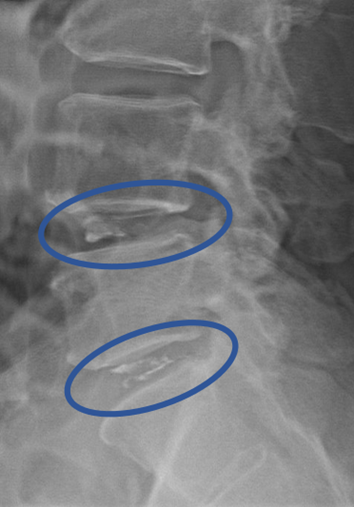

DiscoGelを入れた後の画像になります。